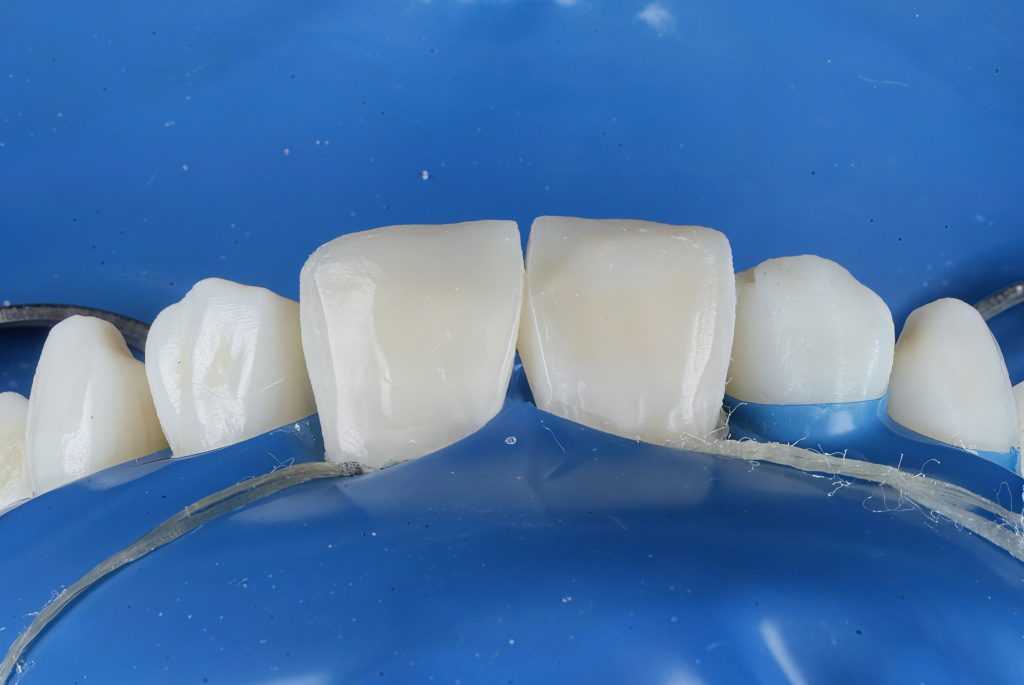

STEP 5 – Heated Composite Injection (Bioclear Technique)

Heated composite (approximately 65–70°C) was injected using the Bioclear anatomical matrices to establish controlled emergence profile, interdental contact, and cervical contour without black triangles. (Fig.5)

STEP 6 – Bio-Emulative Composite Layering

A dentine core was built using 3M Filtek Natural Shade (Dentine Match) to reproduce internal warmth and chroma.

An enamel shell was layered with Clearfil Majesty ES-2 (Enamel Body Shade), selected for ideal light reflection and surface diffusion.

Swiss Spare Mic translucent composite was added to mimic incisal halo, translucency and opalescent zones, enhancing depth.

Grey-white tint characterisation created natural developmental brightness. (Fig.6–7)